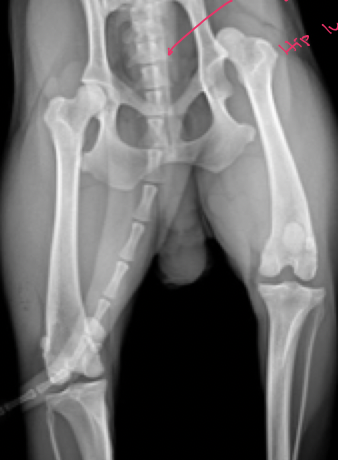

Femoral Capital physeal fracture

Craniodorsal hip luxation

tx

Ehmer sling

makes it abduct

Caudoventral hip luxation

Hobbles

we want to prevent limb from abducting